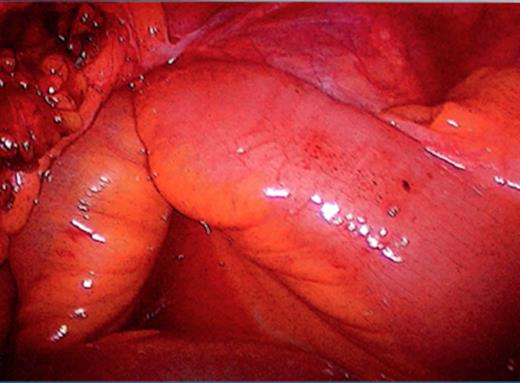

The initial management consisted of a NG tube insertion, IV hydration, and serial abdominal exams. Later, the patient was taken to the operating room due to the significant worsening of her pain. The abdomen was insufflated via the umbilicus with a Veress needle and a 5mm port was placed. Extensive adhesions were visualized throughout the pelvis which was carefully divided. The majority of the small bowel was normal in appearance (Fig. 3), but a segment of 1.5 feet was ischemic and surrounded by dense adhesions (Fig. 4).